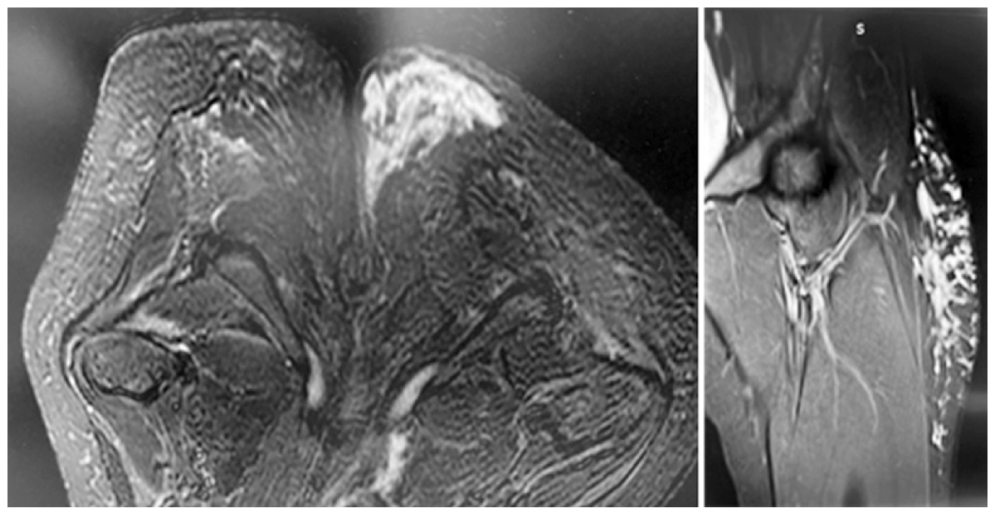

Выполнена магнитно-резонансная томография (16.11.2022): выявлена картина распространённого отёка подкожной жировой клетчатки промежности справа, параректальной и ягодичной области с наличием гнойного содержимого. Данных за объёмное образование органов малого таза, костно-деструктивные изменения позвоночника не получено (рис. 1).

Рис. 1. Магнитно-резонансная томография от 16.11.2022.

Fig. 1. Magnetic resonance imaging on Nov 16, 2022.